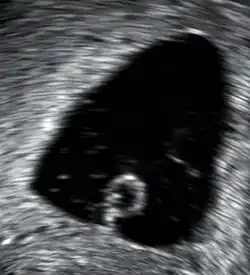

Abortivfrucht

Dies ist eine Fehlentwicklung eines befruchteten Eis, bei der die Embryonalanlage verkümmert ist oder ganz fehlt. Die Abortivfrucht (auch Windei genannt) geht in den ersten Schwangerschaftswochen zugrunde. Bei 50–90 % der Spontanfehlgeburten im 2. Schwangerschaftsmonat handelt es sich um ein Abortivei. Als Ätiologie werden neben genetischen Defekten auch äußere Faktoren wie Intoxikation und Sauerstoffmangel erwogen. Die Gebärmutter wächst nicht. Subjektive Schwangerschaftssymptome sind nur schwach ausgeprägt, teils bestehen Schmierblutungen. Die Diagnose wird nach einer Ultraschalluntersuchung gestellt. Die Schwangerschaftsanlage misst meist weniger als 3 cm. In der von Chorionzotten umgebenen leeren Fruchtblase befindet sich kein Embryo (obwohl sich seit 1995 mit modernen Ultraschallgeräten auch manchmal kleine Embryoblasten sichtbar machen lassen; möglicherweise handelt es sich dann um frühe Formen des verhaltenen Abortes). Als Therapie kommt eine Kürettage in Betracht, es kann aber auch der natürliche Abort abgewartet werden.